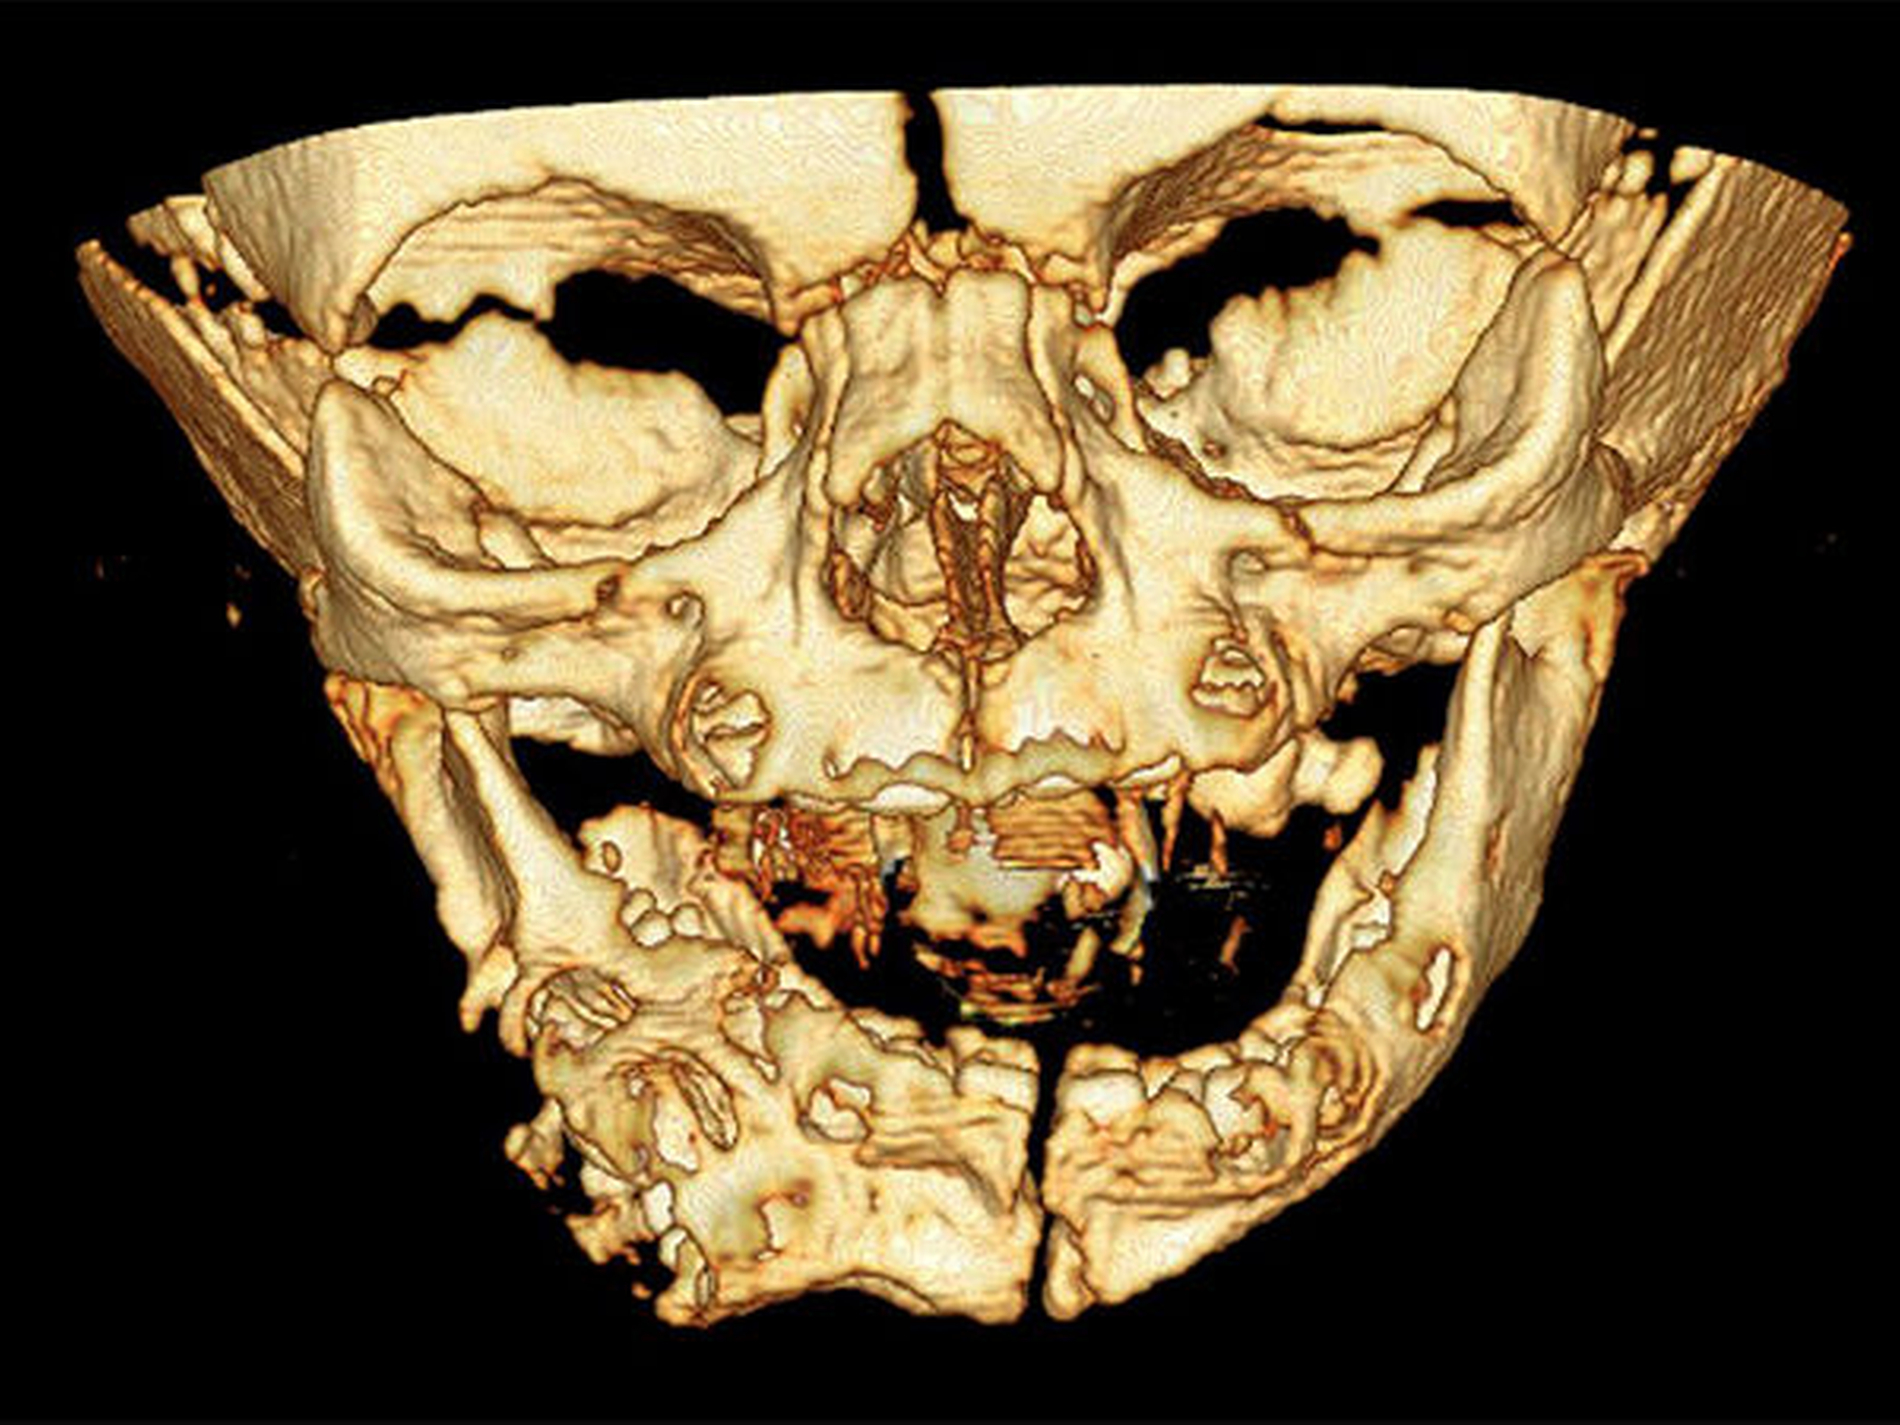

Auf den MRT- und CT-Aufnahmen des Unterkiefers nach der Geburt sieht man eine teilweise verknöcherte Weichgewebemasse, die nicht durchgebrochene Zähne enthielt. Die Atmung und die Nahrungsaufnahme waren nicht eingeschränkt.